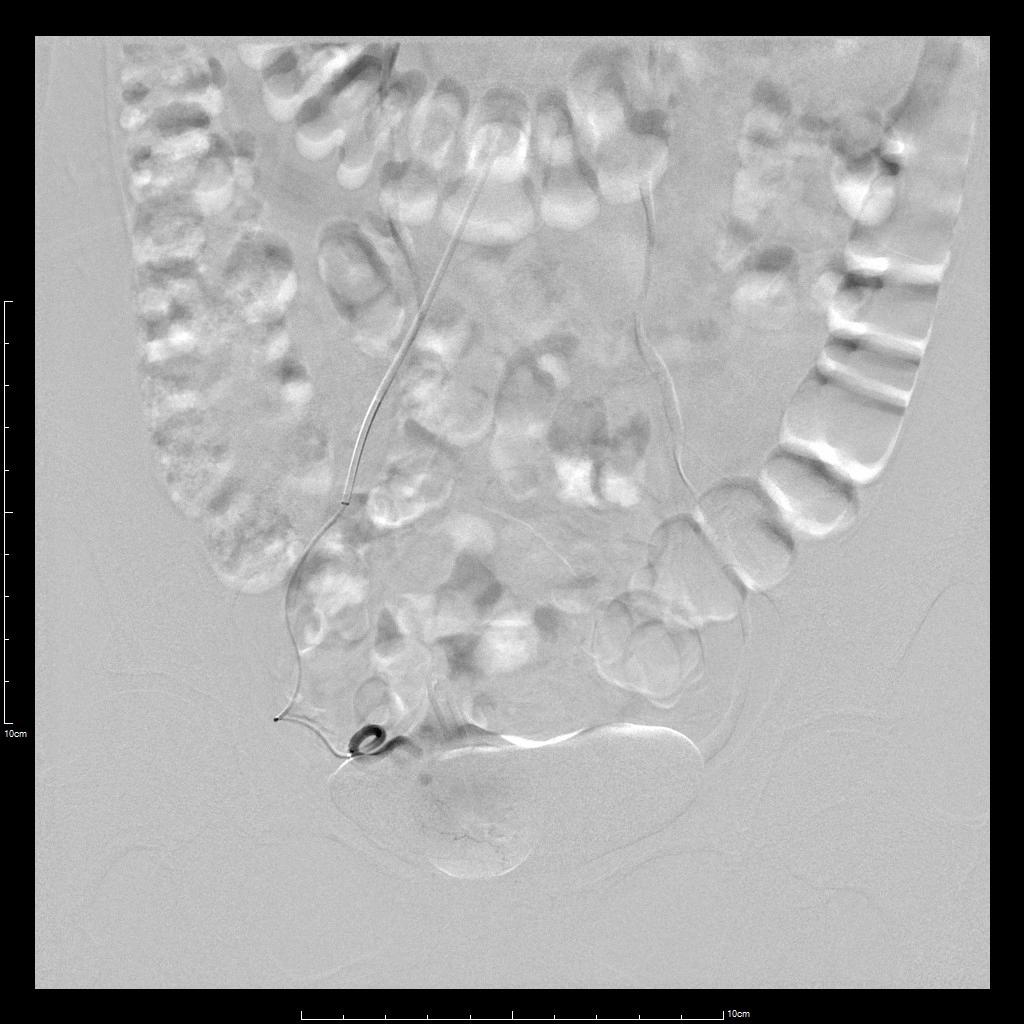

- 超选择插管右侧子宫动脉病灶供血动脉造影+栓塞治疗。

- 超选择插管左侧子宫动脉病灶供血动脉造影+栓塞治疗。

- 术后桡动脉压迫止血6小时,患者术后无需长时间卧床、下肢制动,舒适度明显提高,促进术后快速康复。